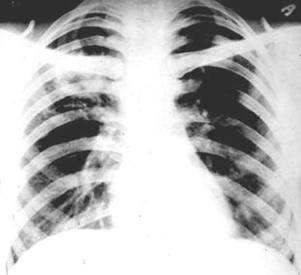

Рентгенологические изображения и синдромы патологии легких